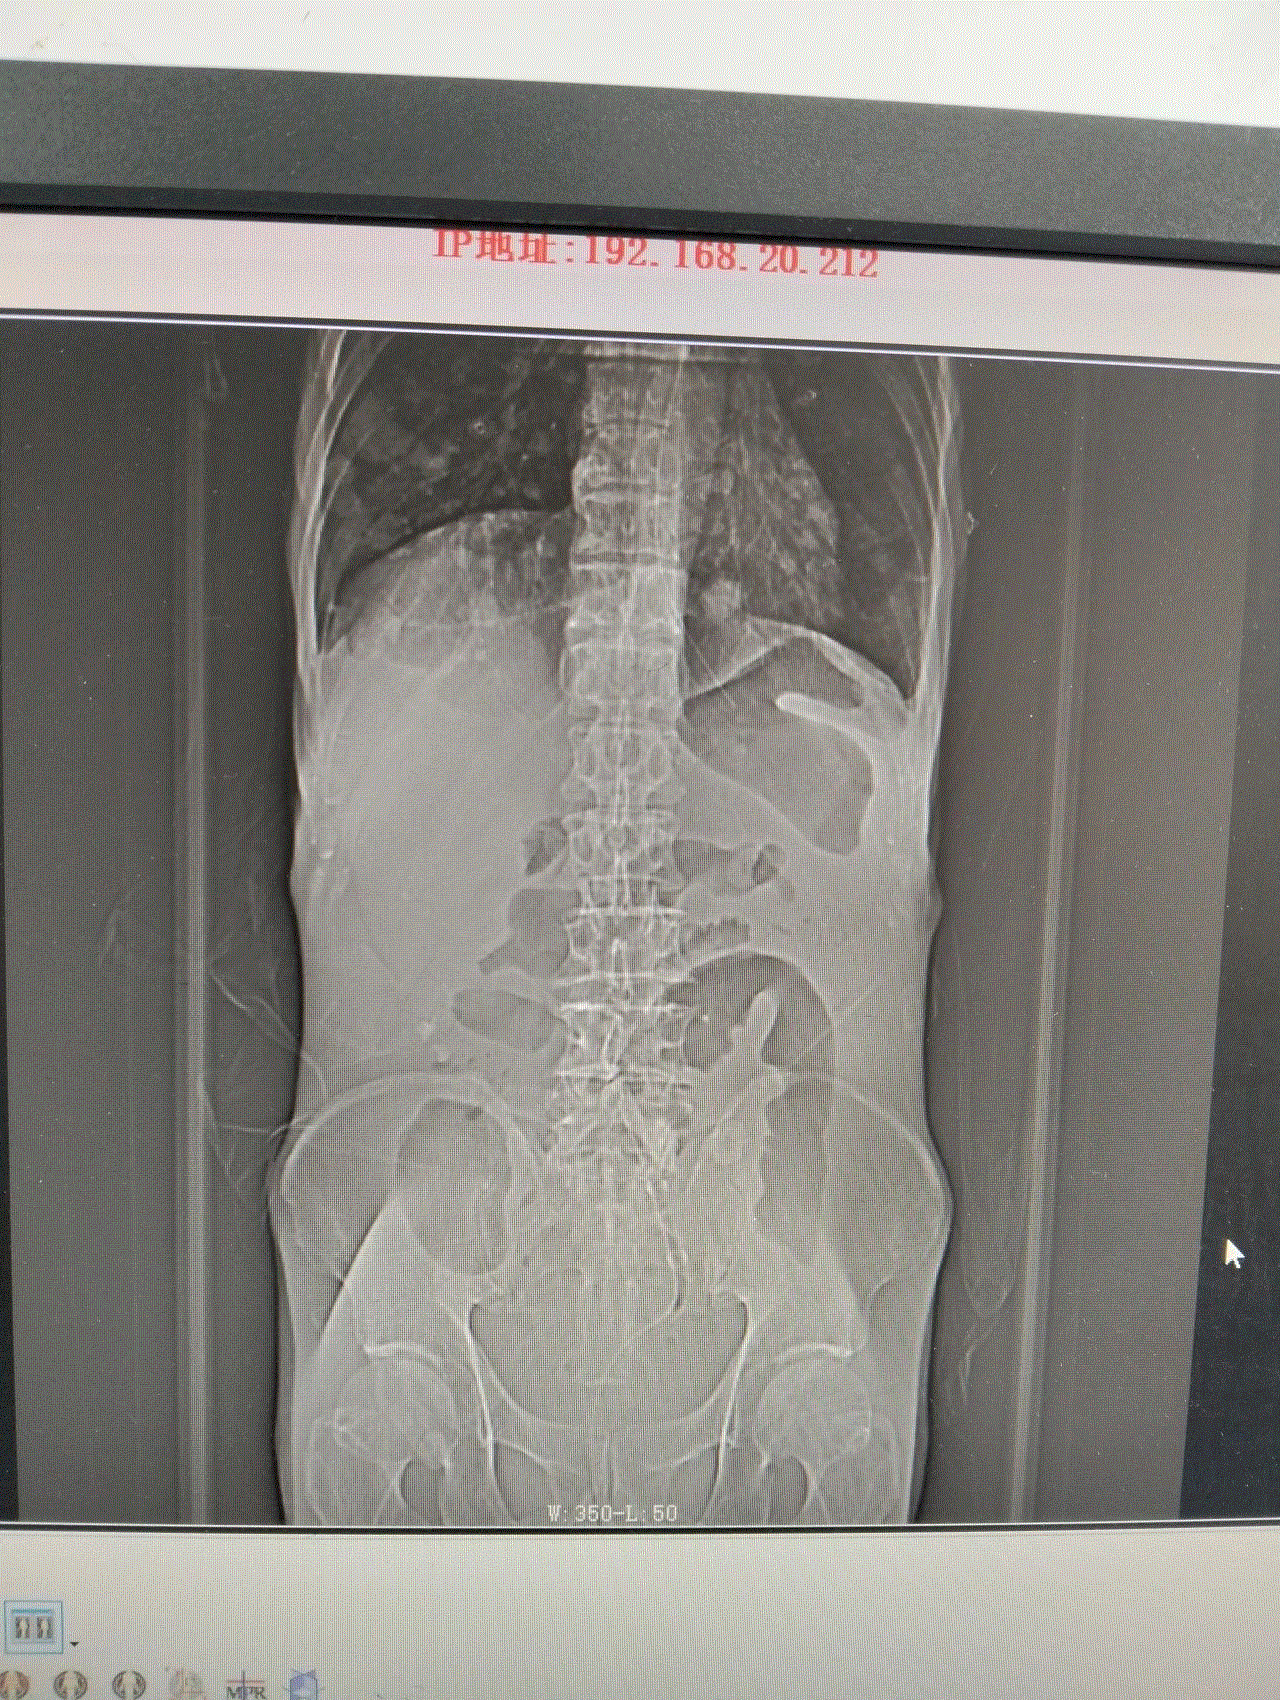

此时的龚大爷,腹部高高隆起,犹如临产的孕妇,叩诊鼓音明显,情况危急!CT显示,龚大爷的结肠严重扩张,脏器被挤压移位。若不及时解除梗阻,随时可能引发腹膜炎、感染性休克,甚至危及生命。然而,常规胃肠减压对低位肠梗阻效果有限,治疗陷入僵局。